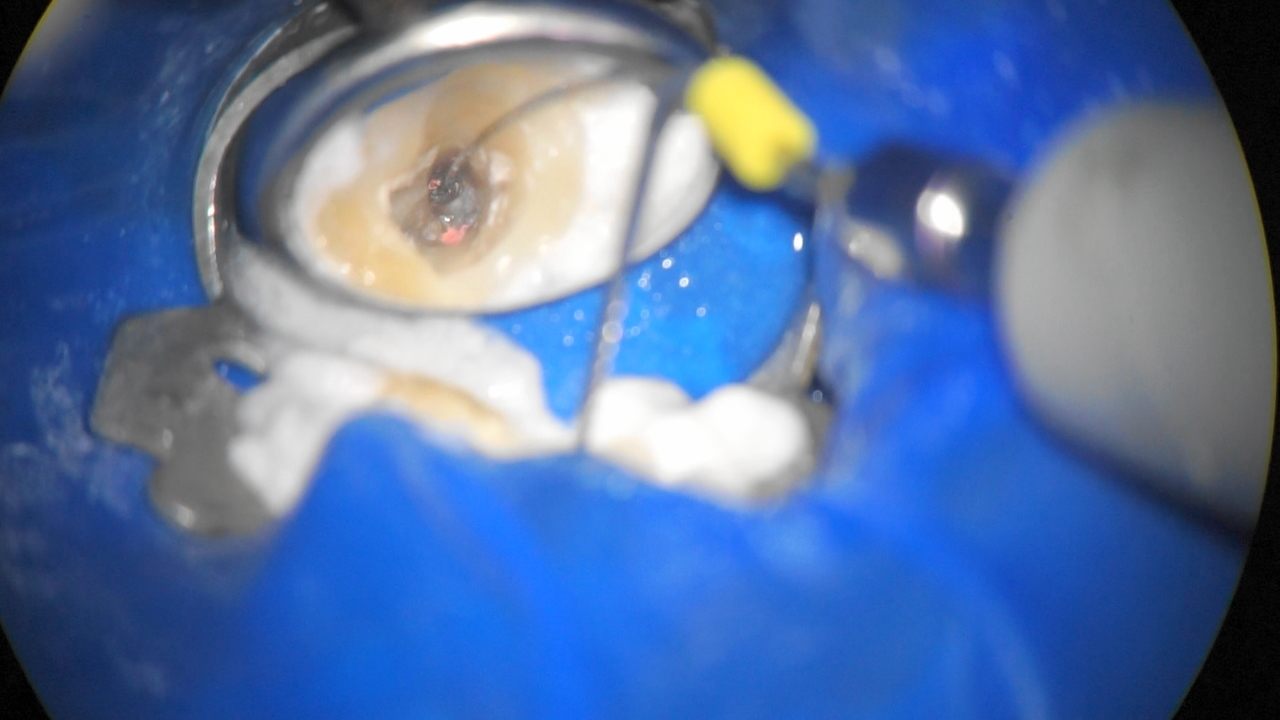

• レッジ(人工根管)、パーフォレーション(人工穴)により腫れが退かなかった上顎第2大臼歯の根の治療

上の奥歯の根の治療をしたが、腫れが引かず耳鼻科でも歯が原因ということを言われセカンドオピニオンで来院されました。何度か同じ歯の治療しているとのことで、精査のためにCTを撮影しました。

腫れの原因は恐らく

①レッジ(人工根管)+パーフォレーション(人工穴)+感染

②本来の根管が未処置(壊死歯髄が残存)が原因の可能性と考えました。

レッジとは湾曲根管(曲がっている根管)で起きる現象です。器具が本来の曲がった根っこに進まずに、ひっかかってしまい上図のようにまっすぐに削れてしまう現象です。そして、誤った方向に穴をあけてしまうことを穿孔(パーフォレーション)といいます

なので治療内容は、①本来の根管に器具を通して清掃

②人工的に穴が開いてるところをセメントで埋める

ということになります。

治療開始

まずは古い充填剤のゴムを丁寧に除去していきます

そして、清掃していくと

・・・・あった!!

人工穴(レッジ+パーフォレーション)と本来の根管を見つける事ができました。

この後、症状が消失したので、パーフォレーション部はMTAセメント、本来の根管はガッタパーチャ(ゴム)を充填しコア(土台)+クラウンを装着して無事治療終了となりました。